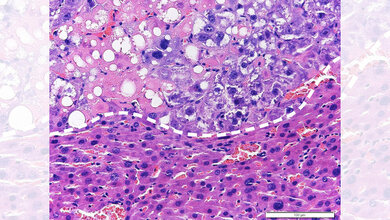

PHx sind oftmals nötig. Sie stellen bei verschiedenen Lebererkrankungen, vor allem aber bei Tumoren eine wesentliche und die oftmals die einzige Säule der kurativen Therapie dar. Obwohl die Entfernung von (Krebs)-Gewebe für die Patientinnen und Patienten lebensnotwendig sein kann, führt sie dennoch zunächst zu einem Gewebeschaden. Das Forschungsteam konnte zeigen, dass geschädigte Zellen sofort eine Immunantwort des Körpers auslösen, welche die Geweberegeneration fördert. Details dieser Kette an Immunreaktionen liegen der medizinischen Wissenschaft jetzt für weiterführende Forschungen unter anderem zur Verbesserung von Wundheilungsprozessen vor.